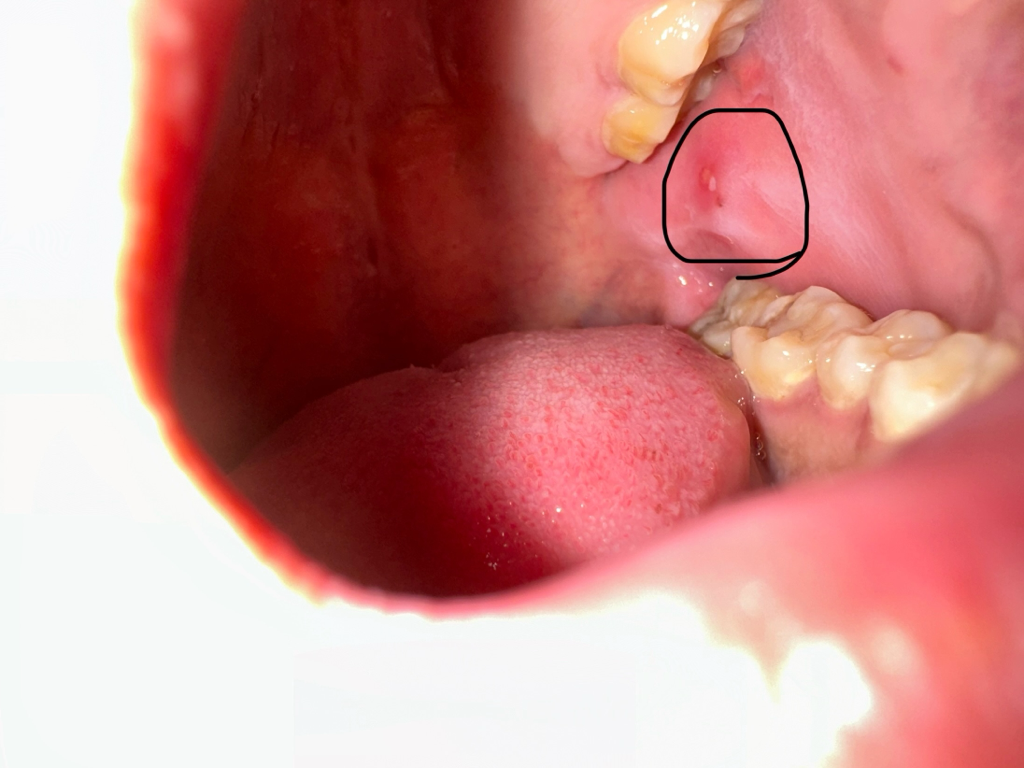

저부분은 잇몸이 치아에 씹혀서 생긴 흔적입니다. 크게 문제가 잇는건 아니니 너무 걱정하지 않으셔도 됩니다.

현재 사진상으로는 해당부위가 부어 있고, 염증이 있어 구내염으로 보입니다. 크게 문제가 되어 보이지는 않으나 보다 정확한 상태 확인을 위해 치과 진료를 받길 권합니다.

사진상으론 구내염으로 보여집니다 최근 피로했다면 구내염이 생길 수 있고 일주일 정도 후면 사라지고 증상도 나아집니다 입 안에 바르는 연고 같은 것을 적용하면 증상 완화에 도움이 됩니다